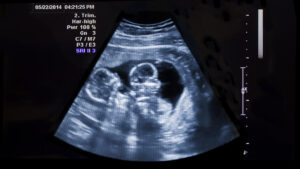

Aprovada na sessão da última segunda-feira (31), a indicação do vereador Dilmair Callegaro (PSDB),sugere ao Executivo Municipal o envio de um projeto de lei instituindo um benefício assistencial de caráter financeiro para familias com gestação múltipla, ou seja, dois ou mais nascituros.

Segundo o vereador o município não dispõe de benefícios para atender familias com filhos gêmeos ou múltiplos e o projeto, se aprovado, pode dar a essas familias um auxilio para minimizar as elevadas despesas com a criação dos filhos.